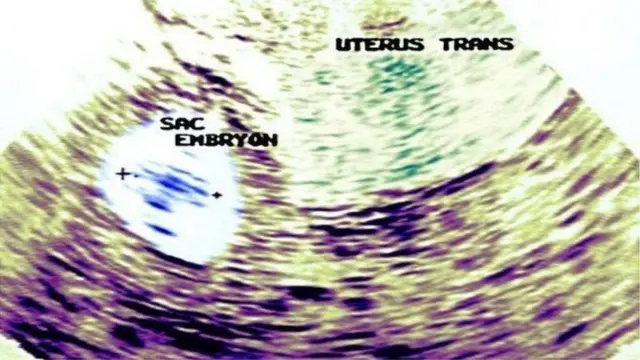

ઇમેજ સ્રોત, DR.SAILAJACHANDU

મહિલા ગર્ભવતી બને ત્યારબાદ પ્રથમ ત્રણ મહિનામાં સ્કેનિંગ કરવામાં આવે છે. તેમાં ભ્રૂણનો સામાન્ય વિકાસ થઈ રહ્યો છે કે નહીં અને મોલર પ્રેગનન્સીને લગતા કોઈ ફેરફાર છે કે નહીં તે ચકાસવામાં આવે છે.